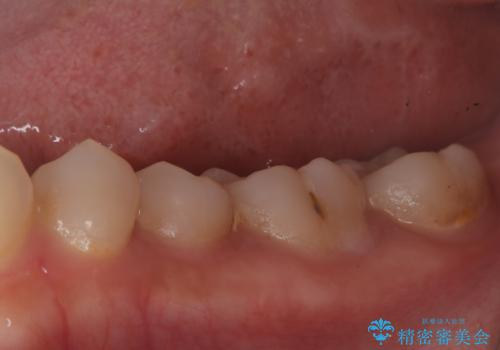

- 昨日からのズキズキとした激しい痛みを主訴にご来院されました。レントゲンおよび歯髄診察の結果、不可逆性の歯髄炎(歯の神経の重度の炎症)と診断。歯を残すことを第一に、まず痛みの原因である神経を取り除く根管治療を提案しました。また、虫歯が歯肉の下まで深く進行していたため、根管治療後に歯周外科処置を行い、最終的に精密なセラミッククラウンで修復する、総合的な治療計画を立案しました。

治療はまず、根管治療から始め、感染した神経を徹底的に除去することで、痛みをすぐに解消しました。再発を防ぐため、ラバーダムや顕微鏡を使って、根管内を丁寧に、そして精密に処置しました。次に、深い部分の虫歯を確実に治療するため、歯周外科処置を行い、治療しやすい環境を整えました。最後に、機能と見た目に優れたセラミッククラウンを作製・装着。根管治療から外科処置、審美修復までを一貫して行うことで、再発リスクの低い、長期的に安定して使える奥歯を取り戻していただけました。